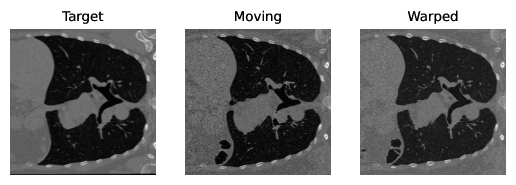

Figure 3 shows qualitative results generated for the NLST and OASIS datasets. Table 2 summarizes the results when comparing RWCNet with LAPIRN on the NLST and OASIS datasets. RWCNet outperforms LAPIRN on both datasets. However, the difference in Dice is only 0.7%, which might be entirely explainable by random weight initialization in network training. For the NLST dataset, the difference in performance is much more pronounced, with the difference in average TRE being 3mm. These results suggest that the architectural features of RWCNet, significantly aid generalization performance in the more challenging large-displacement setting.

| (b) NLST sample results |